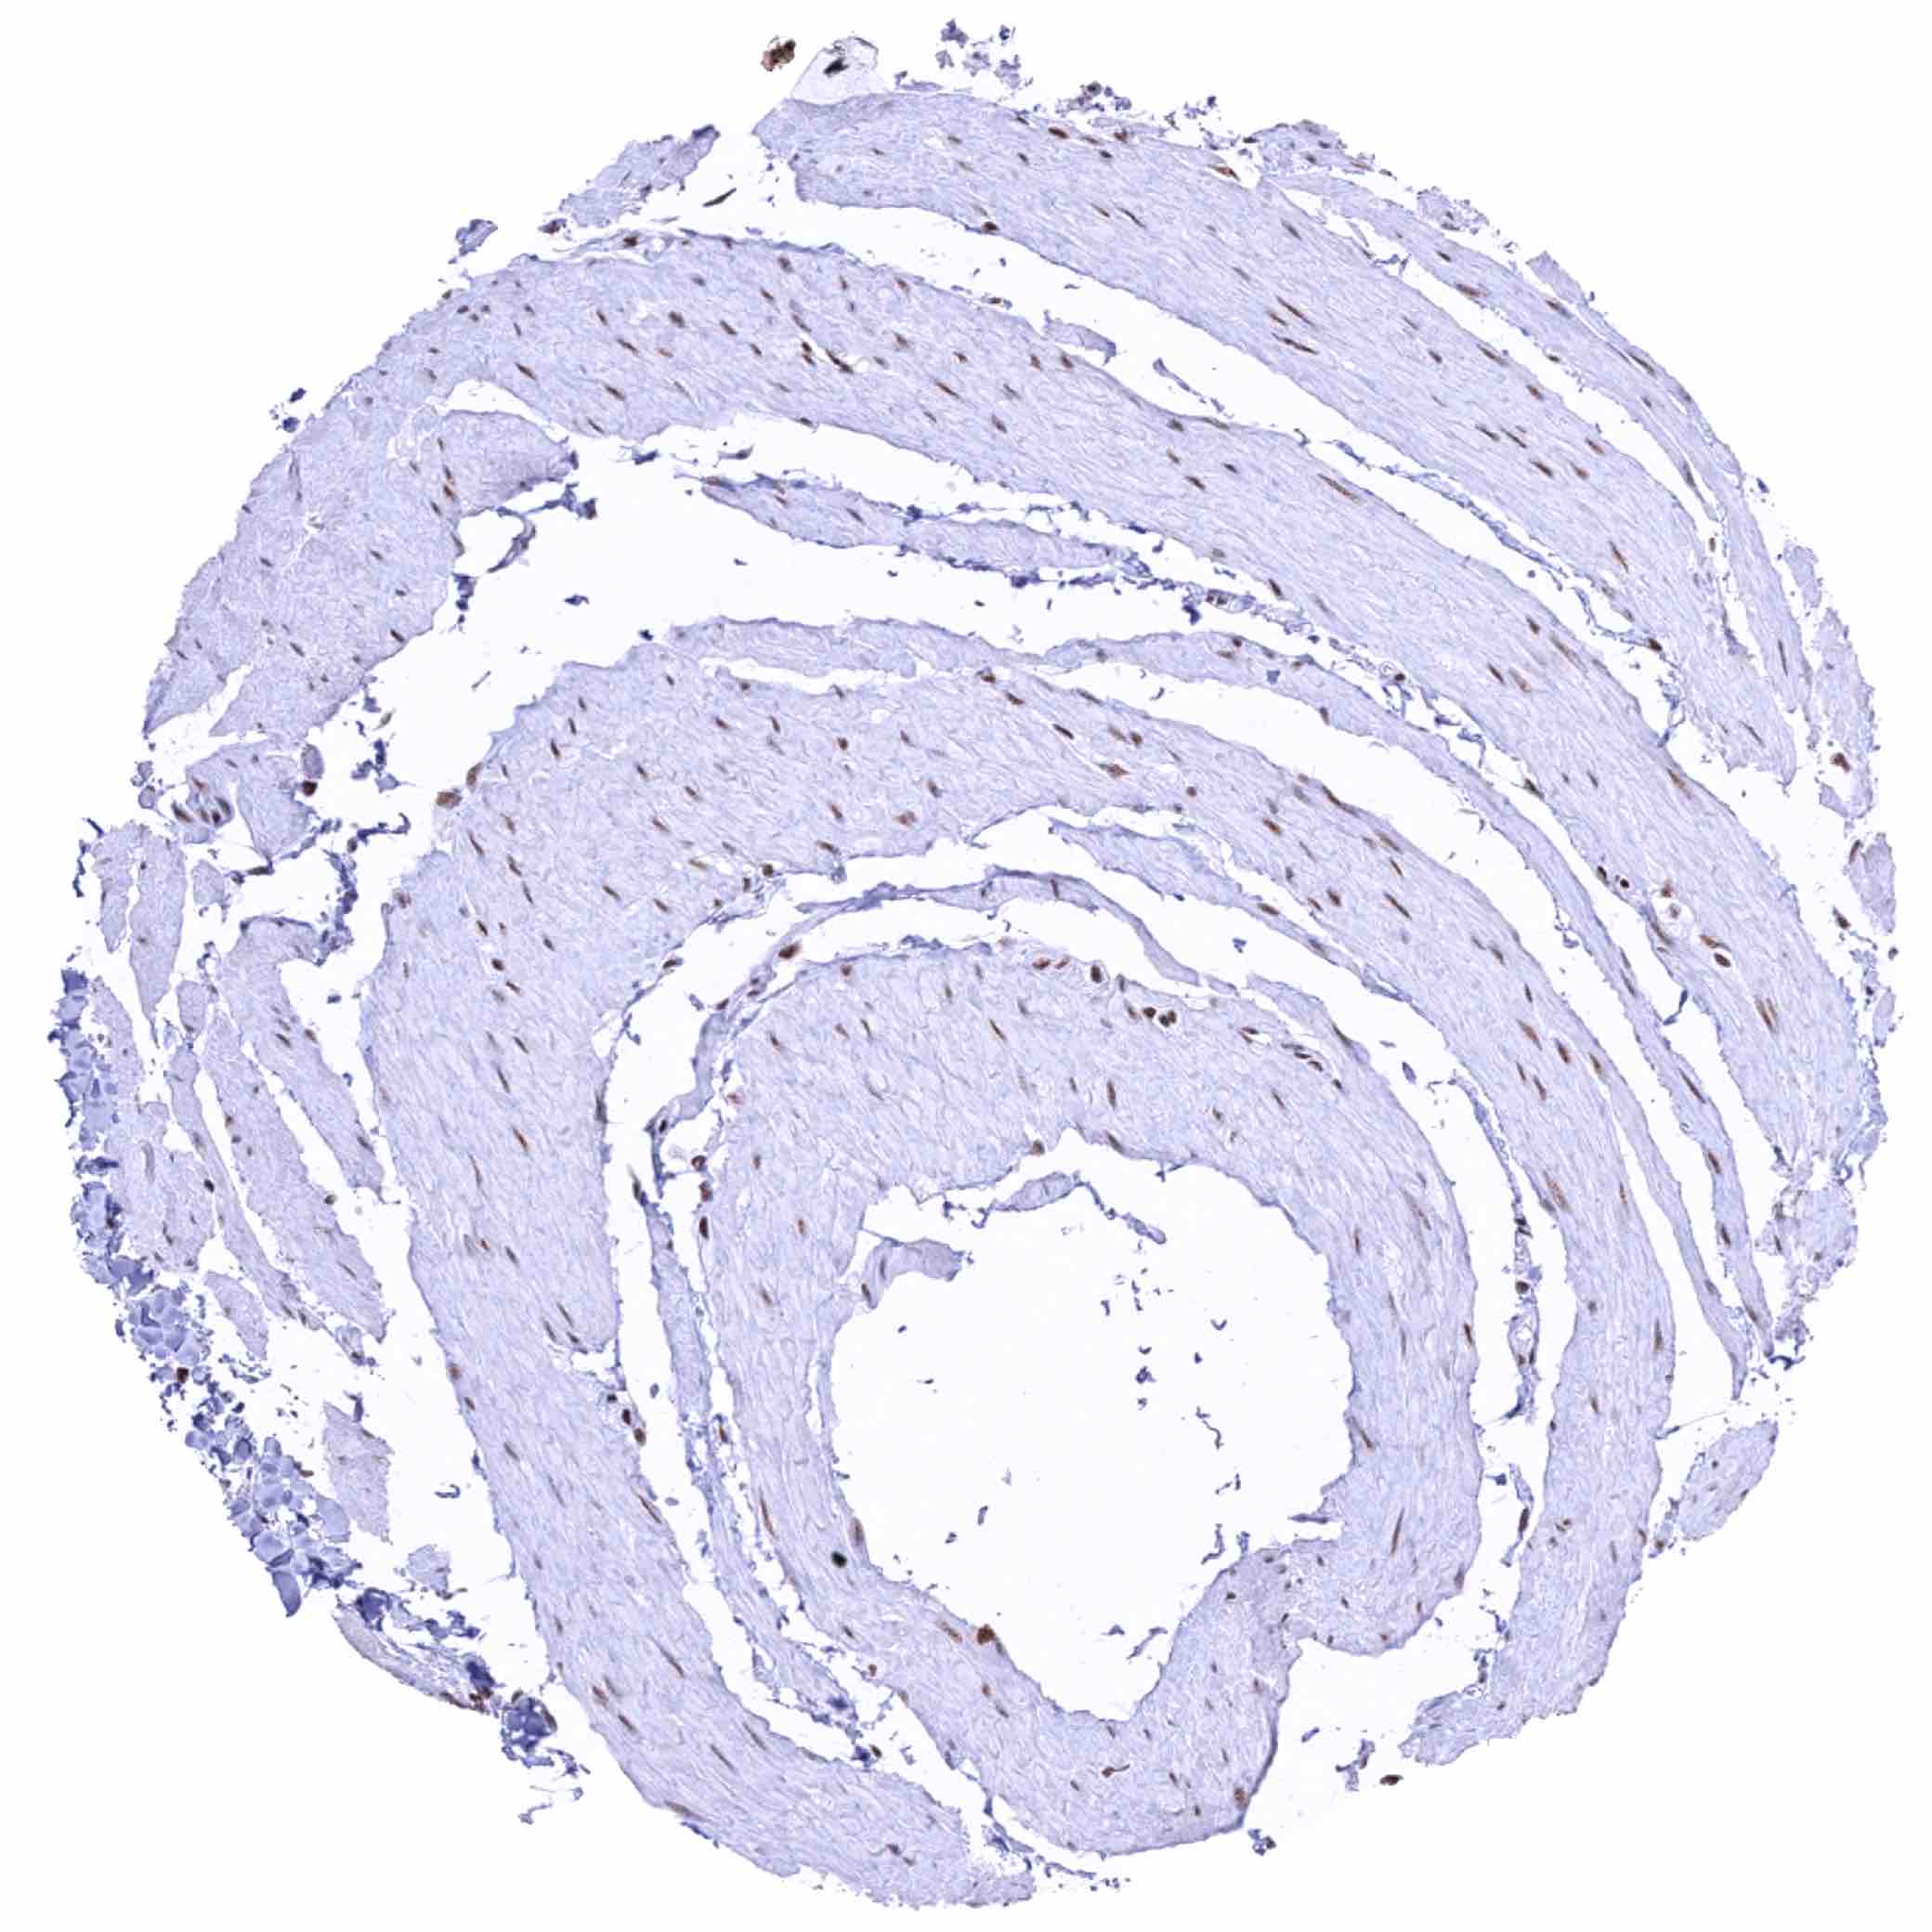

Urinary bladder, muscular wall – Weak to moderate nuclear KDM6A staining of muscular cells